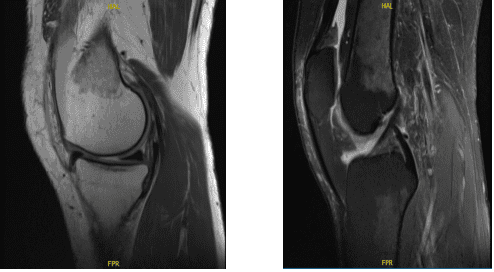

A 47 year-old patient presents with left knee pain that began one week ago. She works as a hemodialysis nurse at SBU and is out of work due to this pain. She is having pain, swelling, buckling and the swelling has decreased. She tried conservative management but had no benefit. The doctor advised her to do an MRI.

MRI was performed, reviewed and discussed by the doctor; the findings stated the Collateral Ligaments: The medial collateral ligament is intact. The lateral collateral ligament, biceps femoris tendon, iliotibial band, and popliteus tendon is intact.

Cruciate Ligaments: The anterior and posterior cruciate ligaments are intact. Menisci: The medial meniscus is intact. The lateral meniscus is intact. The Cartilage: There is a 9 x 6 mm full-thickness chondral defect in the midportion of the medial femoral condyle.

The chondral surfaces in the lateral compartment are intact. There is a focal area of chondral fissuring and partial-thickness cartilage loss in the central trochlea. Bones: The visualized osseous structures demonstrate normal bone marrow and cortical signal intensity without evidence of fracture, trabecular bone injury or dislocation.

No osseous lesions are identified. The Extensor Mechanism: The quadriceps and patellar tendons are normal. Joint: Large knee joint effusion. The soft tissues are otherwise normal. The neurovascular structures demonstrate normal course.

It has an impression of 9 x 6 mm full-thickness chondral defect in the midportion of the medial femoral condyle. Focal area of Chondral fissuring and partial-thickness cartilage loss in the central trochlea. Intact medial and lateral meniscus.

MRI-3T Left knee non-contrast